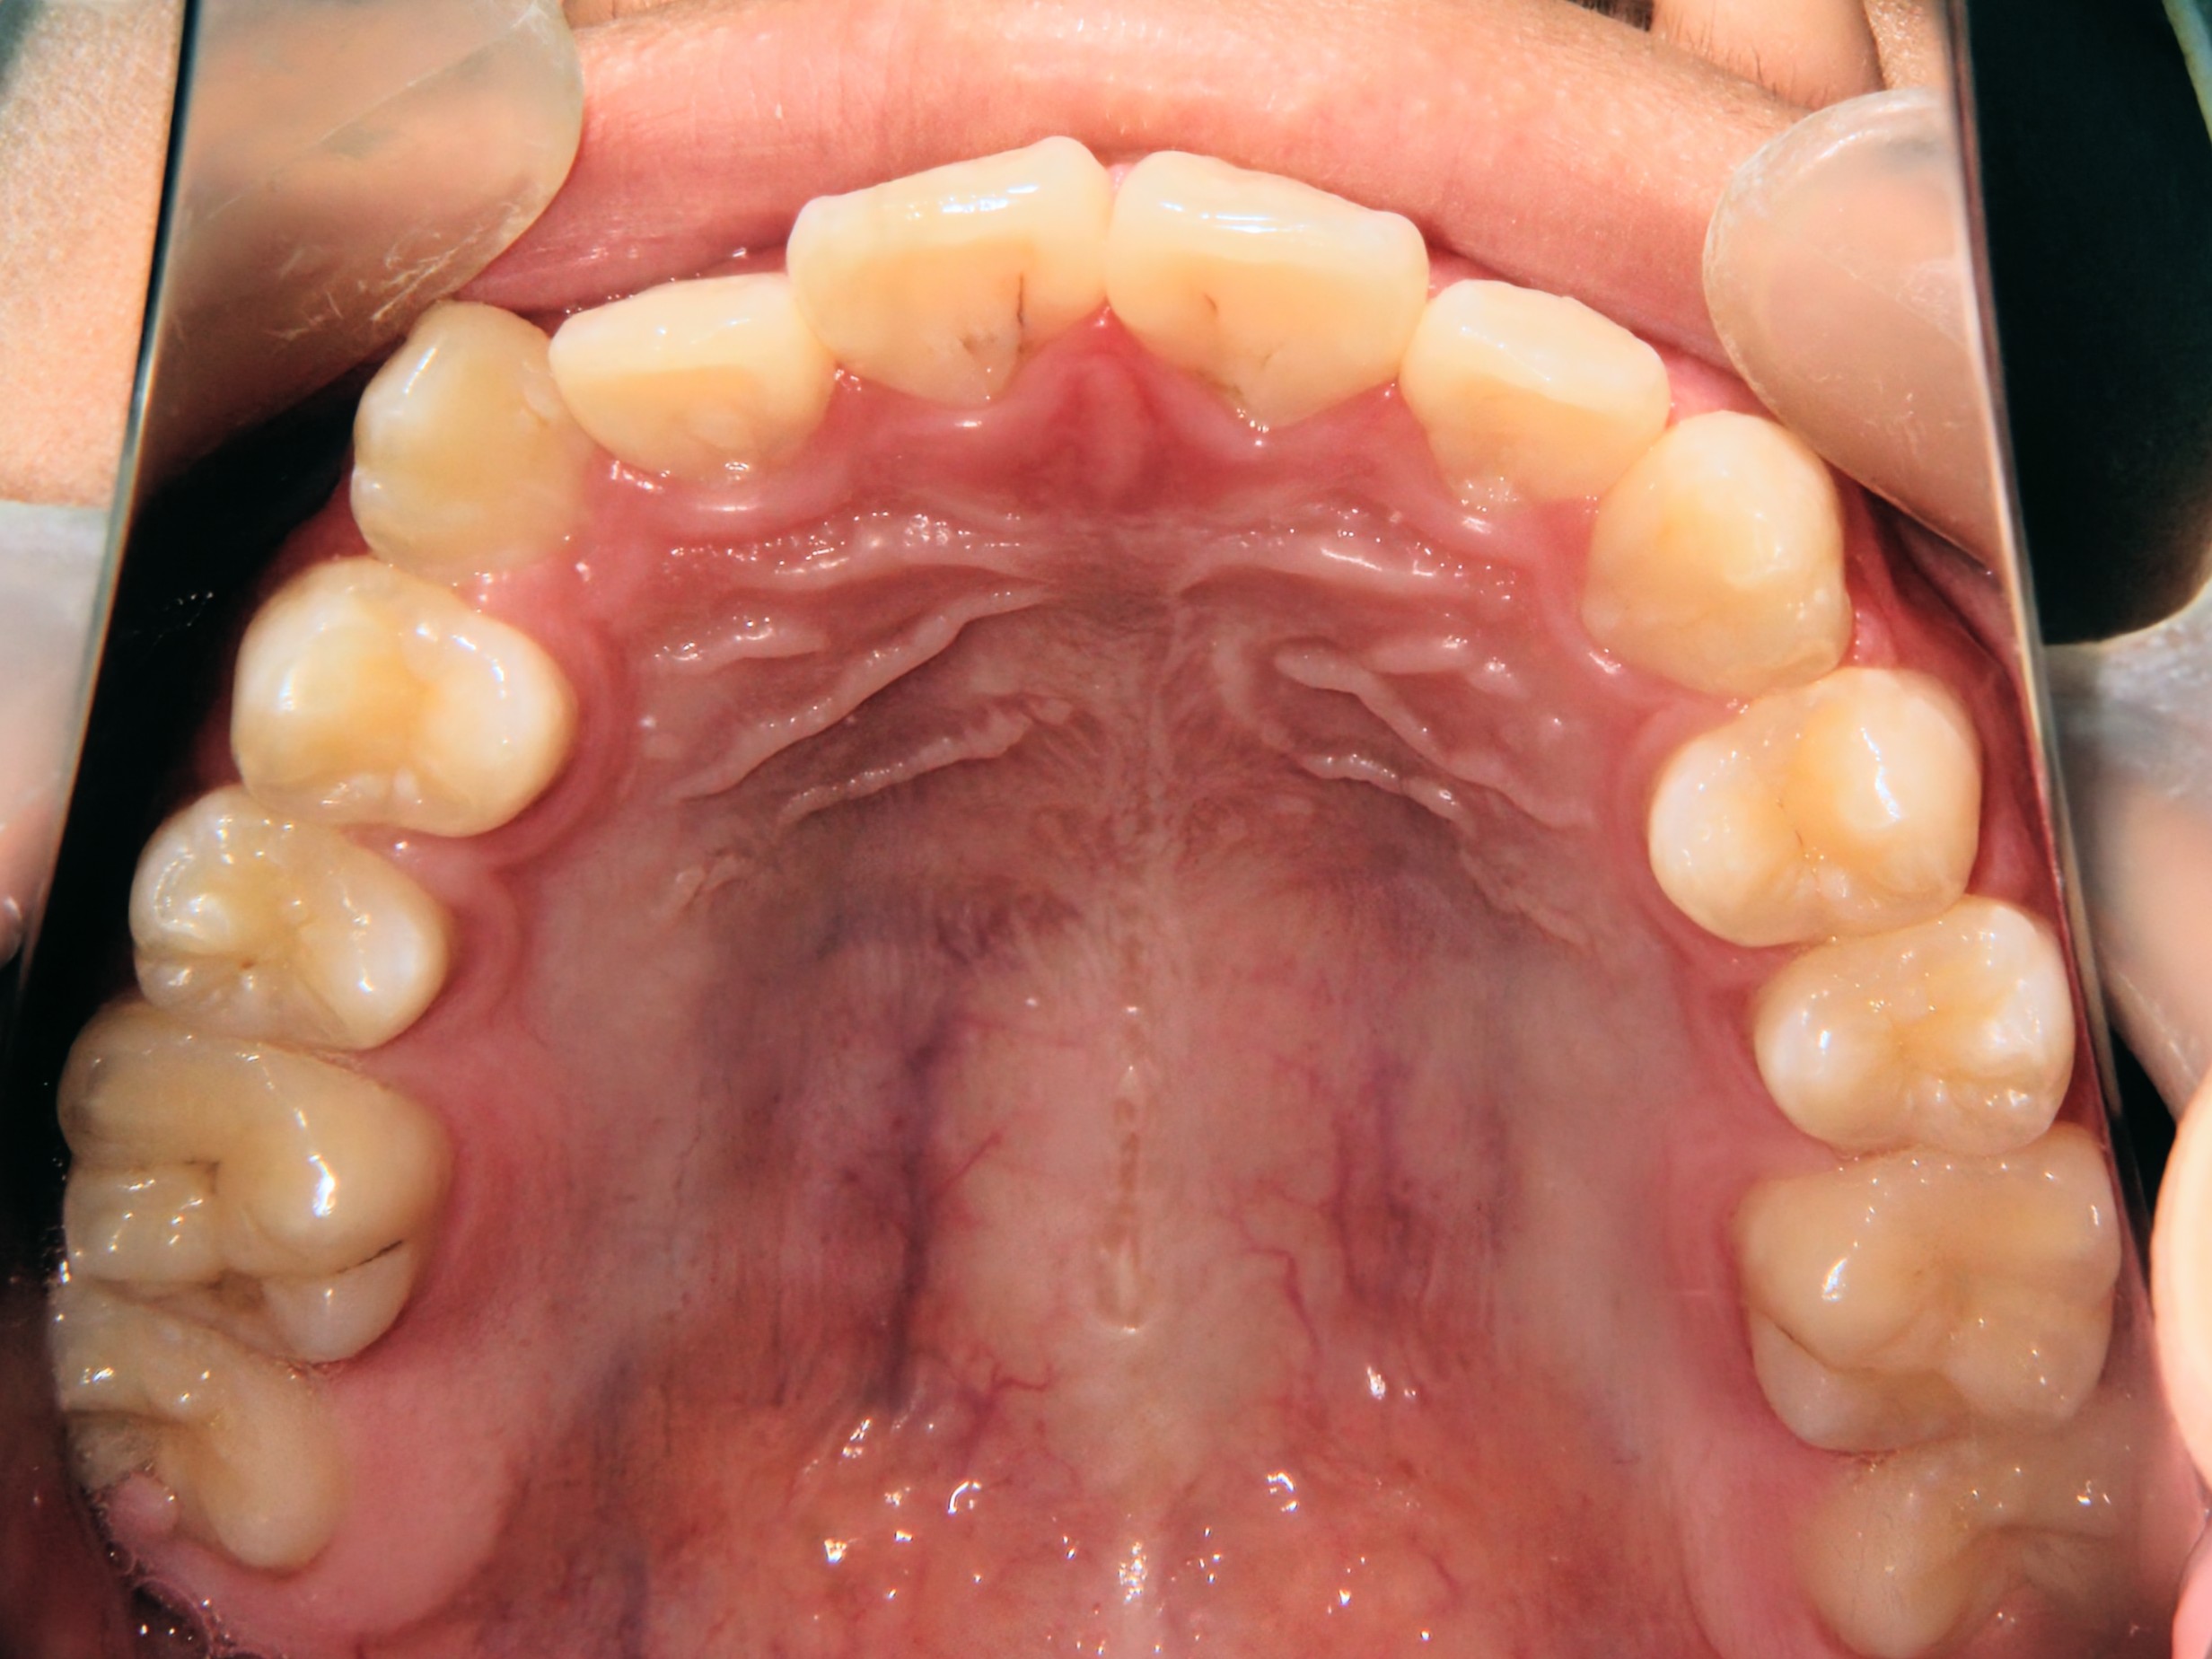

第1期治療終了時

口腔内写真

治療結果

上の前歯のデコボコが改善

上の歯の狭さが改善

目標の永久歯萌出スペースを確保

第2期治療へ移行

上の前歯の裏側に保定装置(Fixリテーナー)を装着し、全ての永久歯萌出後に全顎矯正を行い、全体的な咬み合わせの調整を行います。

経過観察期間:2年7か月